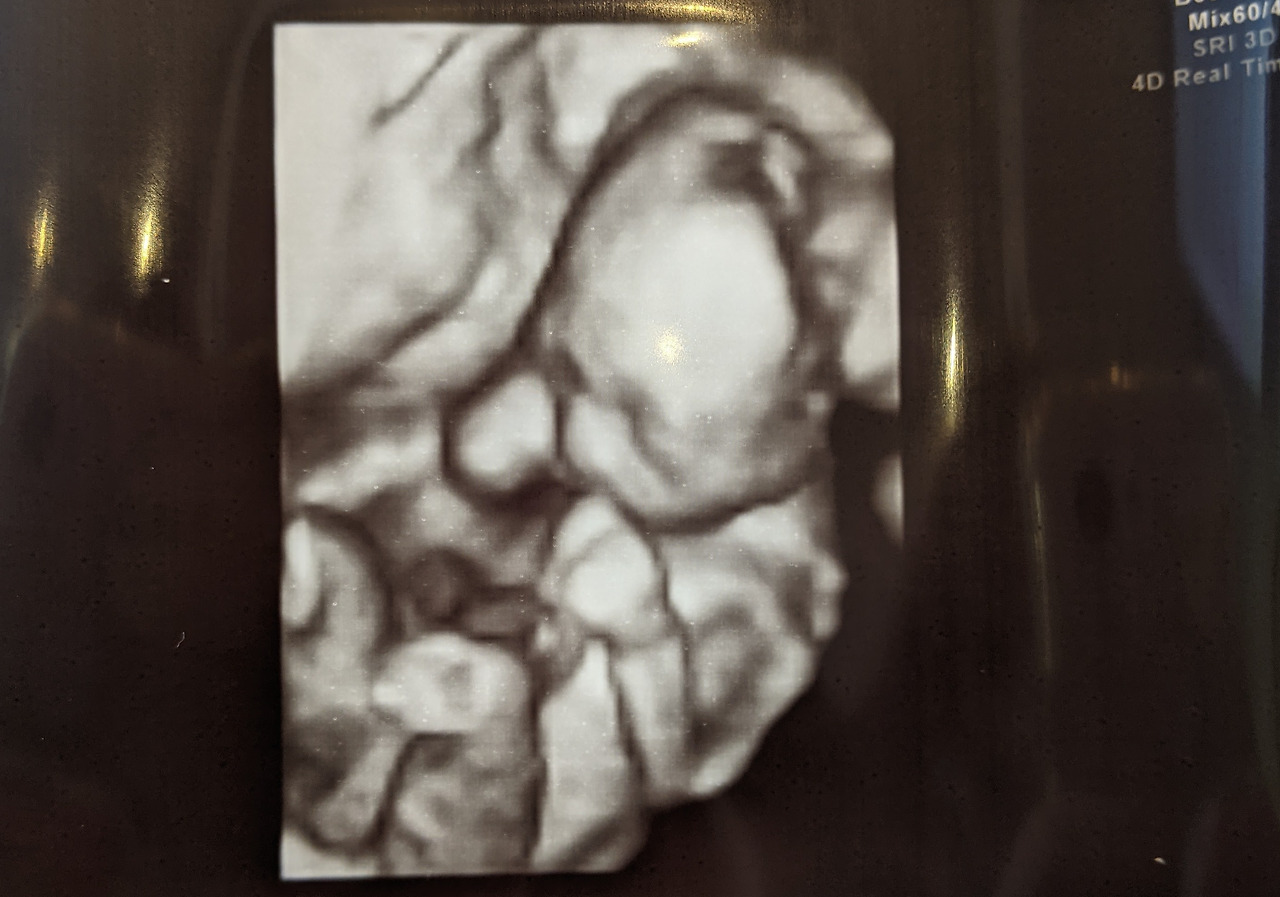

#4 はじめてみるあなたの顔(처음 보는 너의 얼굴)

임신 5개월째, 처음으로 우리 아기의 얼굴을 봤다. 눈, 코, 입, 귀 다 있는 얼굴을 보니 안심도 되고 감동스러워서 눈물이 났다. 손을 꽉 쥐고 웅크리고 있는 모습도 너무나 귀여웠다.

얼굴을 보자마자 "어, 난데?"라는 생각이 들었다. 이목구비가 선명하게 나온 건 아니라 확실히 닮았다고는 말할 수 없지만 동글동글한 느낌이 뭔가 나 같았다. 신랑도 가족들도 다 나랑 비슷한 것 같다고 했다. 과연 실제로는 누굴 닮았을까?

아기는 정말 빨리 자라는 것 같다. 처음엔 초음파 사진에서도 보일까 말까 한 조그만 점이었는데 이제는 이렇게 완전히 사람의 모양을 갖추게 되었다.